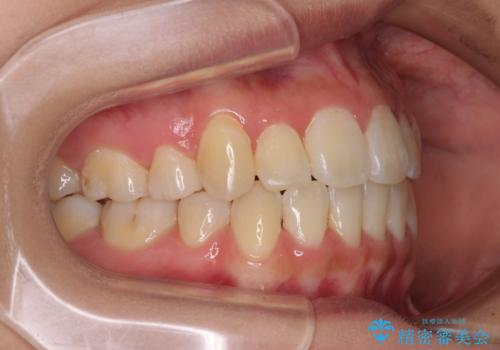

前歯の正中のズレを改善 目立たないワイヤー装置での抜歯矯正

- 八重歯を気にして来院された患者様です。

上下ともに前突感と叢生が認められ、上顎の正中が著しく右側にずれていたため、上下左右第一小臼歯4本を抜歯し、ワイヤー矯正にて治療を行うこととしました。

移動量が多かったため、治療期間は通常より半年~1年ほど長くかかりましたが、上下の正中をほぼ同じ位置にまで移動させることができました。